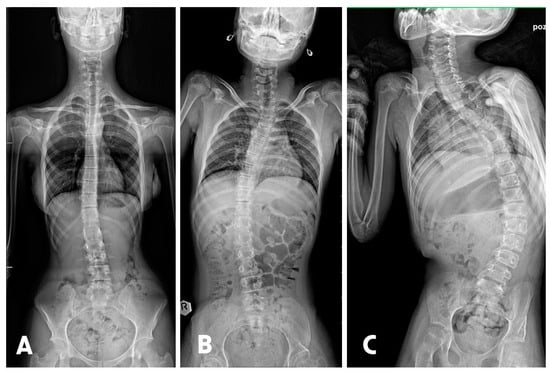

- Fabijan, A.; Fabijan, R.; Zawadzka-Fabijan, A.; Nowosławska, E.; Zakrzewski, K.; Polis, B. Evaluating Scoliosis Severity Based on Posturographic X-ray Images Using a Contrastive Language–Image Pretraining Model. Diagnostics 2023, 13, 2142. [Google Scholar] [CrossRef]